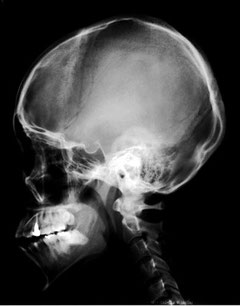

X線撮影(頭蓋骨:Skull)